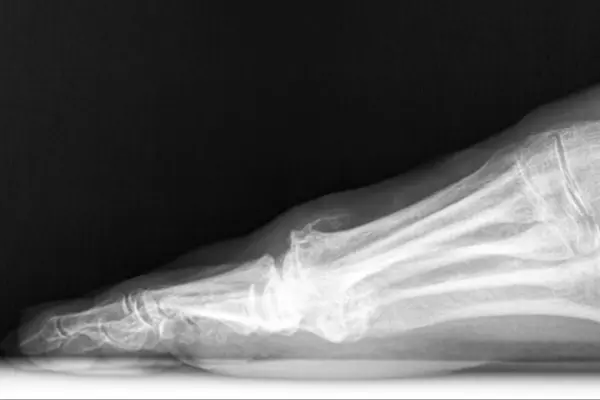

What is Hallux Rigidus?

Hallux Rigidus literally means “stiff big toe.” It develops due to wear-and-tear arthritis, trauma, or genetic predisposition. Patients often complain of pain while walking, difficulty bending the toe, or a visible bony bump on top of the toe joint.

- Cheilectomy Dubai: Removing bone spurs to restore motion.

- Osteotomy: Realignment procedure to reduce joint stress.

- Fusion Surgery UAE: Permanently fuses the joint to eliminate pain in severe cases.